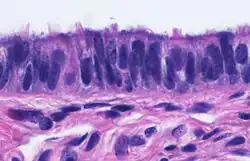

Micrograph of ciliated columnar epithelium of the fallopian tube

When viewed under the microscope, the fallopian tube has three layers.[6] From outer to inner, these are the serosa, muscularis mucosae, and the mucosa.[15][16]

The innermost mucosa is made up of a layer of luminal epithelium, and an underlying thin layer of loose connective tissue the lamina propria.[16] There are three different cell types in the epithelium. Around 25% of the cells are ciliated columnar cells; around 60% are secretory cells, and the rest are peg cells thought to be a secretory cell variant.[4] The ciliated cells are most numerous in the infundibulum, and the ampulla. Estrogen increases the formation of cilia on these cells. Peg cells are shorter, have surface microvilli, and are located between the other epithelial cells.[6] The presence of immune cells in the mucosa has also been reported with the main type being CD8+ T-cells. Other cells found are B lymphocytes, macrophages, NK cells, and dendritic cells.[16]

The histological features of tube vary along its length. The mucosa of the ampulla contains an extensive array of complex folds, whereas the relatively narrow isthmus has a thick muscular coat and simple mucosal folds.[14]